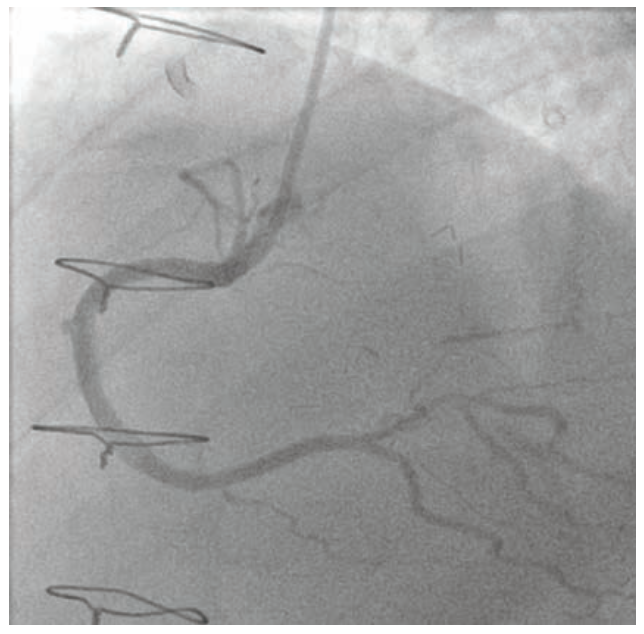

Dual access was achieved with a 7 French Amplatz Left (AL)-1 guide catheter and a 7 French Extra Backup (EBU) 3.75 guide catheter. Based on dual-injection angiography, the proximal cap was ambiguous due to a tortuous right ventricular (RV) marginal branch and the occlusion was long (>20 mm) (Figure 1). Therefore, we decided to attempt retrograde techniques first. After administering heparin to a goal activated clotting time (ACT) of >350, a workhorse wire was advanced through a low-profile microcatheter into the first septal perforator. The wire was exchanged for a specialty wire that was used to cross septal collaterals. We had difficulty advancing the microcatheter into the septal perforator, as it was jailed with a previously placed stent (Figure 2). Here, we used a 1.5 mm x 20 mm TAKERU balloon to dilate the stent struts. We were able to advance the microcatheter into the septal perforator and into the distal vessel (Figure 3). The connection was made with a reverse controlled antegrade and retrograde tracking (R-CART) technique (Figure 4). Overlapping drug-eluting stents were placed and aggressively post dilated. Final angiography demonstrated no residual stenosis, dissection, or perforation (Figure 5). The patient was placed on dual antiplatelet therapy for six months.